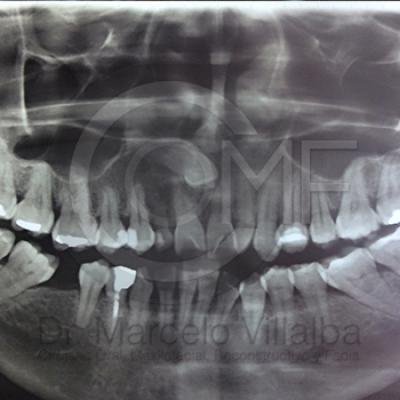

Generalmente en el momento de su erupción presentan procesos inflamatorios en la zona posterior de la cavidad oral, infección, dolor, movilidad de órganos dentarios, mal sabor en boca, mal olor en boca (halitosis), infección, incluso edema (aumento de volumen en tejido blando de la cara y/o boca) y complicaciones si no son atendidos. En el apoyo de diagnóstico se pueden requerir radiografías panorámicas y hasta tomografía en caso de ser necesarios.

Para el tratamiento de estas patologías se necesita en forma inicial estudios de laboratorio, radiografías o tomografías, estos estudios serán solicitados por el especialista a cada caso en particular, siendo su tratamiento quirúrgico bajo la modalidad de anestesia local o anestesia local más sedación consciente se puede realizar el procedimiento en corto tiempo y buen pronóstico.